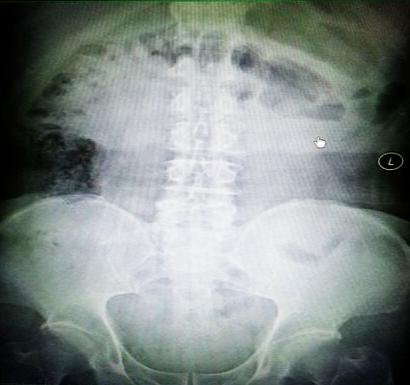

受試患者在結(jié)腸端端吻合術(shù)中,使用我司新研制產(chǎn)品達(dá)到了理想的預(yù)期效果。患者術(shù)后7天、14天X光片顯影,可降解腸道支架均能按研制設(shè)計(jì)的預(yù)期時(shí)間節(jié)點(diǎn)保持應(yīng)有強(qiáng)度,術(shù)后21天X光片顯示可降解腸道支架已完全破碎,并排出體外。在整個(gè)試驗(yàn)過程中,病患無(wú)任何不良反映,耐受良好。